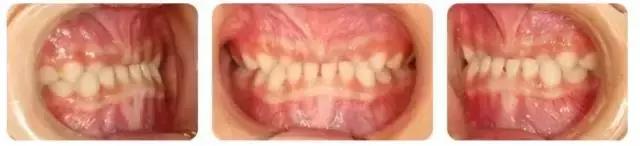

“孩子的牙齿长这样”, 怎么办?

没错,这就是俗称的牙齿“地包天”。

专业地说,儿童乳牙期“地包天”,就是乳下前牙咬合于乳上前牙唇侧,也叫乳前牙反颌,专业上属三类错颌。